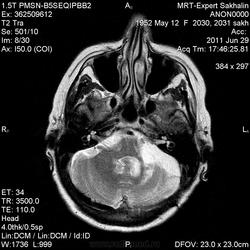

Абсолютно с Вами согласна Helios - это рецидив. Рискну предположить что убирали либо невриному левого тройничного нерва, либо менингиому верхушки пирамиды височной кости.

Со слов сына женщины-удаляли невриному.

согласен за такой рецидив. Если бы удаляли зло- задумался бы.

Нет левого клочка мозжечка что объясняет и головокружение и головные боли ... вместе с узелком образуют клочково-узелковую дольку мозжечка, филогенетически это наиболее древняя часть мозжечка, так что повреждение клочка вызывает очень выраженные и стойкие вестибулярные нарушения ...

Нет левого клочка мозжечка что объясняет и головокружение и головные боли ... вместе с узелком образуют клочково-узелковую дольку мозжечка, филогенетически это наиболее древняя часть мозжечка, так что повреждение клочка вызывает очень выраженные и стойкие вестибулярные нарушения ...